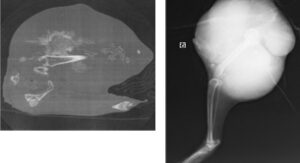

身体検査で歩様異常を認めレントゲン検査を行ったところ骨腫瘍が疑われたためCT検査、生検検査を実施しました。生検では骨腫疑いでしたが進行スピードが早く悪性腫瘍を疑って断脚術を実施しました。結果は悪性の骨肉腫でした。